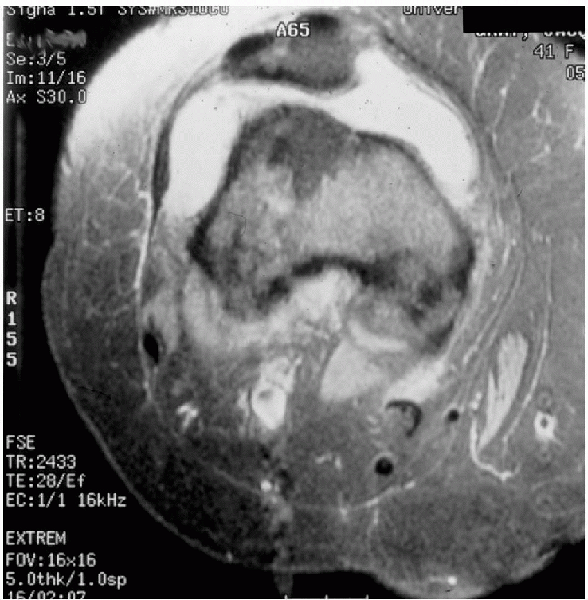

MRI can show lateral condyle bruising and medial retinacular tearing after dislocation (Fig. 5-13).

Figure 5-13 MRI of a knee after patella dislocation, lateral condyle bruising, and medial retinacular disruption are diagnostic.